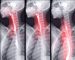

Baryum Yutma Testi, Gastrointestinal sistemimiz, sindirim sürecinin temel taşlarından biridir ve bu karmaşık sistemde zaman zaman çeşitli sorunlar ortaya çıkabilir. … Baryum Yutma Testi Nedir okumayı sürdür